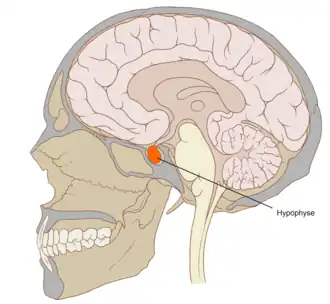

Tumor de hipófisis

Localización de la hipófisis (color rojo) en la base del cráneo. | ||